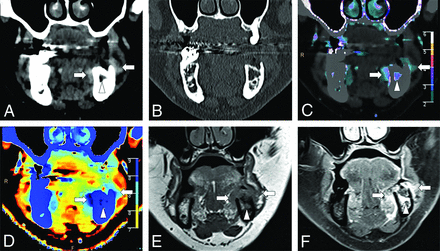

A 63-year-old man with left buccal and alveolar mucosa squamous cell carcinoma (arrows) seen on the conventional images in soft-tissue (A) and bone (B) window settings. Iodine density (B), color iodine density overlay (C), and Z-effective (D) images reveal right mandibular bone invasion with increased iodine density in the medullary cavity of the left hemimandible (arrowhead). T1-weighted MR imaging (E) and post-gadolinium-enhanced T1 fat-saturated (F) image confirm bone marrow infiltration. The patient was upstaged from T3 to T4a.